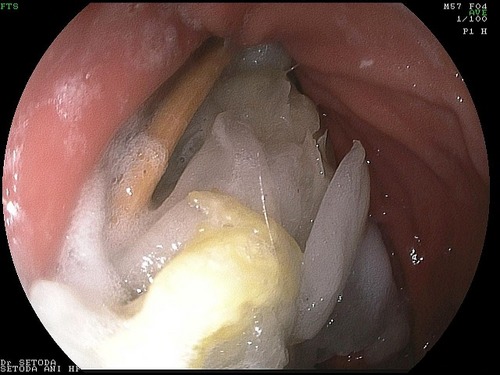

よくあることですが、内視鏡検査をしてみると!

MAE00003.jpg

つまようじが胃から十二指腸の中に入り始めている状態でした。